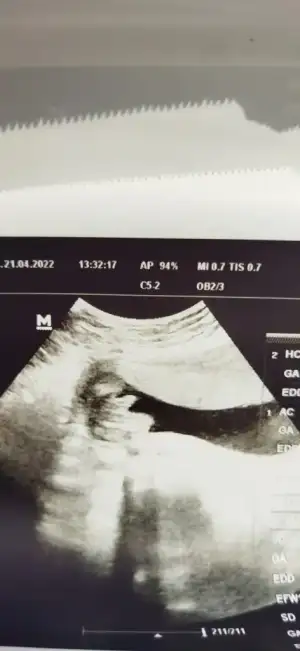

Kızlar kontrolden çıktım 18+1, bebeğim 239 gram 19,67 cm çıktı, çok şükür görünen şeyler yolunda. Bir sonraki kontrolüm 3 hafta sonra, ilk defa bu kadar uzun bekleyeceğim